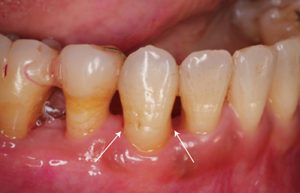

図6 外科的にアクセスした際の垂直性骨欠損と根分岐病変

図7 歯周組織再生療法の実際

右下犬歯を取り囲むように深い歯周ポケットが認められました。成長因子製剤と骨補填材を使用し、外科的に歯周組織再生を図りました。

治療のX線では6か月後、24か月後と犬歯周囲に骨再生が認められます。